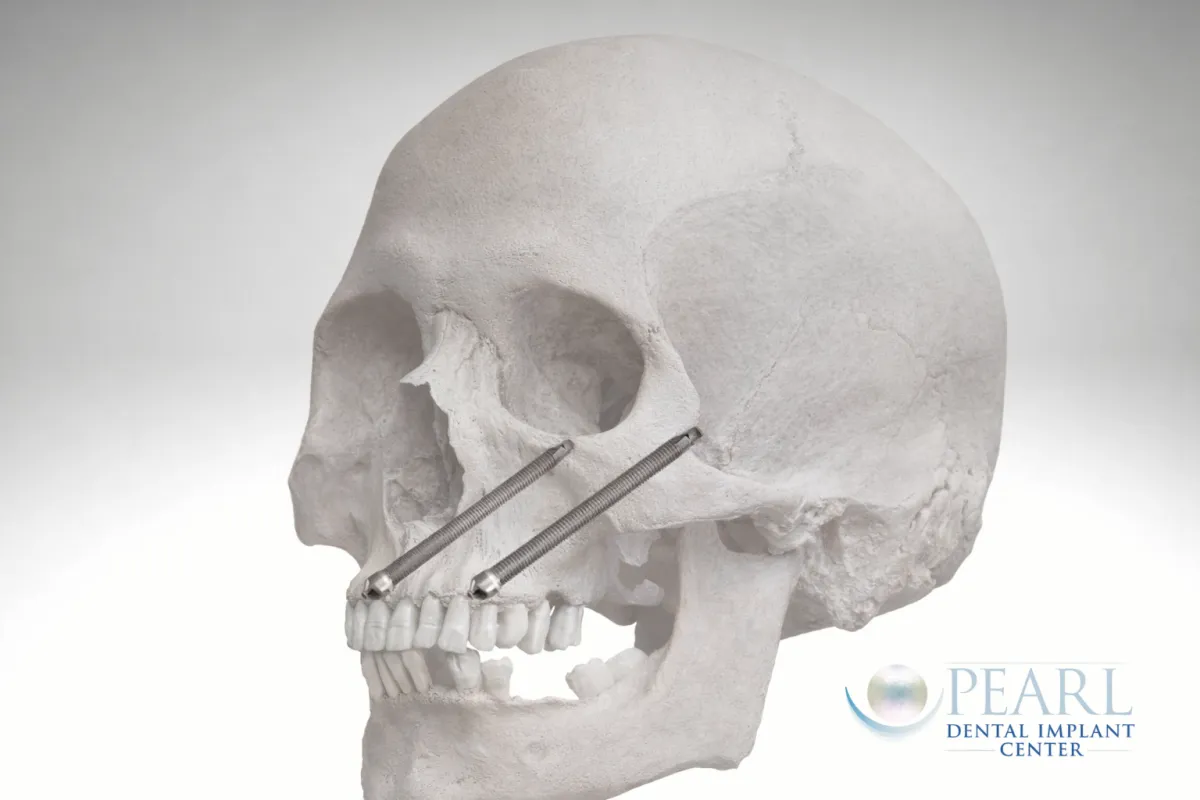

Zygomatic Dental Implants

Advanced implants for severe upper jaw bone loss

Zygomatic dental implants anchor into the cheekbone, offering a full-arch solution for patients who are not candidates for traditional implants.